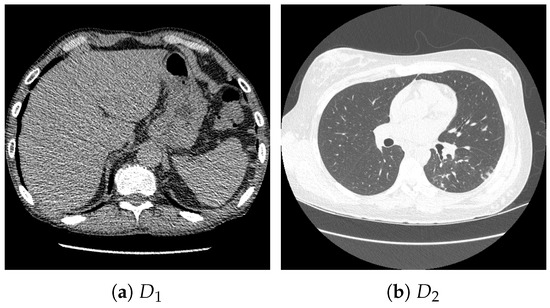

For pretraining, we utilized a subset of the J-MID (https://www.radiology.jp/j-mid/ (accessed on 6 April 2025)) database, which contains large-scale CT scans from Japanese medical institutions, and the RICORD dataset [58], an open dataset that was developed collaboratively by the Radiological Society of North America and international partners and contains chest CT scans collected from four countries. Each dataset was constructed with two domains based on mediastinal and lung window settings in chest CT images. Both domains are denoted as and , and the labels are not used during pretraining. Specifically, for the J-MID subset, (the mediastinal window) contains 31,256 CT images, and (the lung window) contains 26,403 CT images. The RICORD dataset comprises 12,897 (mediastinal window) images and 11,668 (lung window) images for pretraining. For the J-MID dataset, was generated using a window level (WL) of HU and a window width (WW) of HU, whereas was generated using a WL of HU and a WW of HU. For the RICORD dataset, was generated with a WL of HU and a WW of HU, while was generated with a WL of HU and a WW of HU. These parameter ranges were selected to cover clinically standard lung and mediastinal window settings while accommodating inter-scan variability in DICOM metadata. The corresponding images for each example are shown in Figure 2 and Figure 3. For fine-tuning and evaluation, we utilized two public datasets: the SARS-CoV-2 CT-Scan Dataset [59] and the Chest CT-Scan Images Dataset (https://www.kaggle.com/datasets/mohamedhanyyy/chest-ctscan-images (accessed on 6 April 2025)). Both datasets were used for the coronavirus disease 2019 (COVID-19) and chest cancer classification tasks, respectively. The data breakdown is as follows: the SARS-CoV-2 CT-Scan Dataset comprises 1589 training, 397 validation, and 495 test images, labeled into two (COVID-19 and Normal) classes. The Chest CT-Scan Images Dataset comprises 490 training, 123 validation, and 315 test images labeled into four (adenocarcinoma, large-cell carcinoma, squamous-cell carcinoma, and normal) classes. COVID-19 classification and lung cancer classification were selected as downstream tasks because chest CT is widely used in clinical practice for diagnosing both COVID-19 and lung cancer, allowing for an evaluation that closely reflects real-world clinical scenarios. Accordingly, to ensure reproducibility and enable fair comparisons with prior studies, we prioritized the use of publicly available datasets. The corresponding images for each example are shown in Figure 4 and Figure 5.

Figure 2.

Examples of chest CT images on the subsets from the J-MID database: (a) first-domain dataset () and (b) second-domain dataset ().

Figure 3.

Examples of chest CT images on the subset from the RICORD dataset: (a) and (b) .